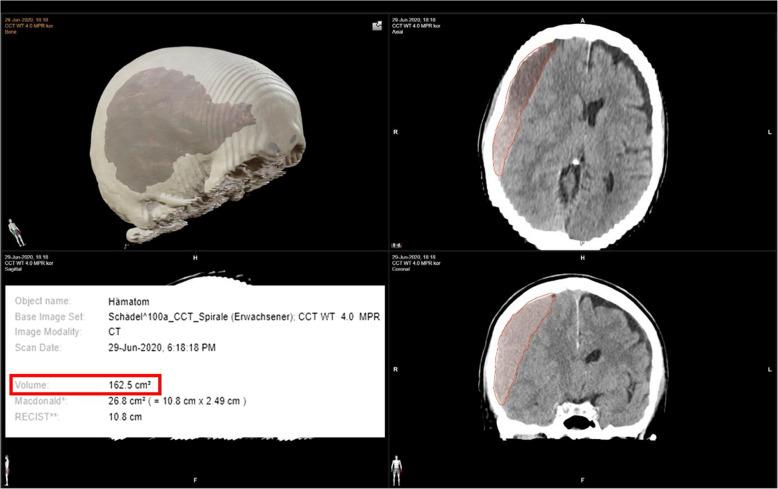

TABASCO is a prospective, randomized, two-arm, multicenter, clinical trial designed to determine whether postoperative treatment of chronic subdural hematomas using adjuvant drug therapy with tranexamic acid (test group) is equivalent to postoperative embolization of the arteria meningea media (control group) in terms of postoperative volume reduction of the hematoma and the need for revision surgery of CSDH. Patients over 18 years of age who have undergone surgery for CSDH for the first time no more than 24 h before inclusion in the study will be randomized 1:1 to the test group or control group. The primary endpoint is the postoperative volume decrease of a primarily surgically relieved CSDH quantitatively and regarding to the time course on the affected side in a study period of 3 months postoperatively. The secondary endpoint of this study is to investigate the extent to which the rate of necessary revision surgery can be influenced by the adjuvant therapy procedures over the course of 3 months. The tertiary endpoint is the neurological outcome of the patients included in the study and assigned to the different treatment arms after a total follow-up period of 3 months as well as the complication rate of the adjuvant procedures used. Assuming a risk difference of 8% for rebleeding and surgical revision, with an applied power of 80%, 276 patients (138 per group) will be included in this study.

TABASCO是一项前瞻性、随机、双臂、多中心临床试验,旨在确定使用氨甲环酸辅助药物治疗(试验组)与脑膜中动脉术后栓塞(对照组)在慢性硬膜下血肿术后血肿体积缩小和CSDH翻修手术需求方面是否等效。在纳入研究前不超过24小时首次接受CSDH手术的18岁以上患者将按1:1随机分为试验组或对照组。主要终点是在术后3个月的研究期内,定量并根据患侧的时间进程,评估主要通过手术缓解的CSDH术后血肿体积的减少情况。本研究的次要终点是调查在3个月的过程中,辅助治疗程序能在多大程度上影响必要的翻修手术率。第三终点是在总共3个月的随访期后,纳入研究并分配到不同治疗组的患者的神经学结果以及所用辅助程序的并发症发生率。假设再出血和手术翻修的风险差异为8%,检验效能为80%,本研究将纳入276例患者(每组138例)。